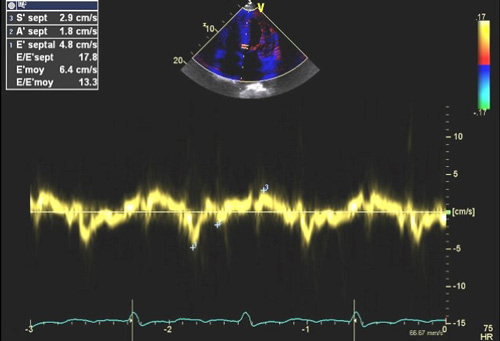

La dilatation des oreillettes est fréquente et s’associe à une dysfonction diastolique. Les pressions de remplissages VG sont souvent élevées (Figure 2) sauf à un stade préclinique chez certains patients a- ou peu symptomatiques. L’étude de la fonction diastolique ventriculaire gauche est basée sur une approche multiparamétrique intégrant le Doppler pulsé mitral, le DTI à l’anneau mitral, le volume de l’oreillette gauche (>32-34 ml/m² SC) et la Vmax du flux d’IT (>2.8 m/s) permettant également d’estimer les pressions artérielles pulmonaires (PAPS).

Figure 2 : Pressions de remplissage VG élevées souvent élevées en cas d’amylose cardiaque évolutive.

Exemple de pressions de remplissages élevées chez un patient avec amylose cardiaque : E/A >2, E/E’ moyen = 13, volume biplan indexé de l’OG > 34 ml/m² SC, Vmax de l’IT proche de 2.8 m/s